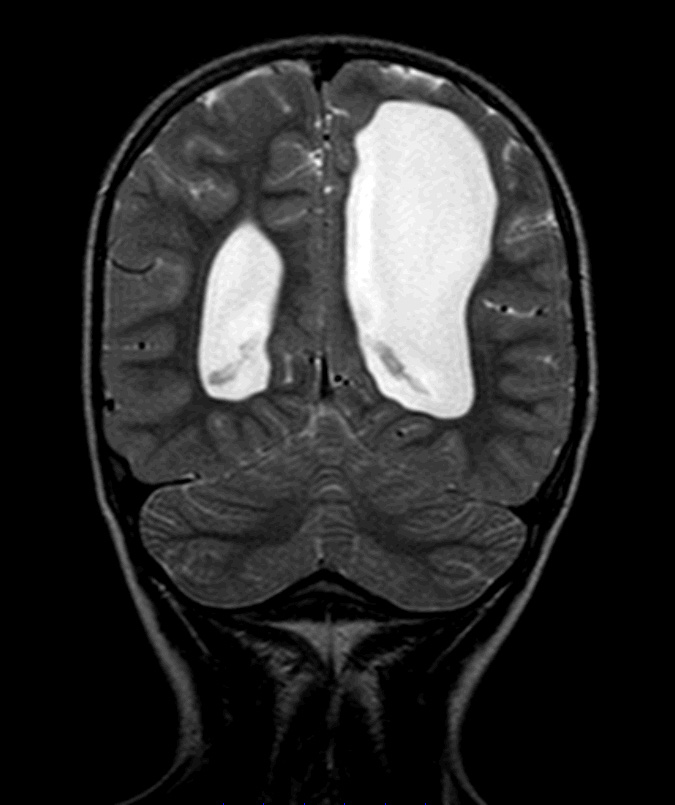

Rinorreia Crónica: Rinite ou Algo Mais?

Criança, Diagnóstico por Imagem, Rinorreia, encefalocelo/diagnósticoDownloads